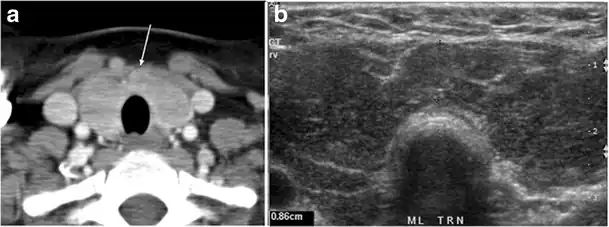

Fig. 16. Midline ectopic thyroid with Hashimoto's thyroiditis in a 49-year-old female patient. a Transverse greyscale ultrasound shows a 1.6 × 0.8 cm solid, well-defined, heterogeneous area (white arrow) in the midline, superior to the thyroid gland. It is iso-echogenic to the thyroid gland with no definite connection to the thyroid gland. b Transverse colour Doppler ultrasound shows significant increase in vascularity. c Axial enhanced neck CT scan at the level of thyroid cartilage demonstrates midline infrahyoid hyperdense soft tissue mass (white arrow) embedded within the strap muscle.[1]